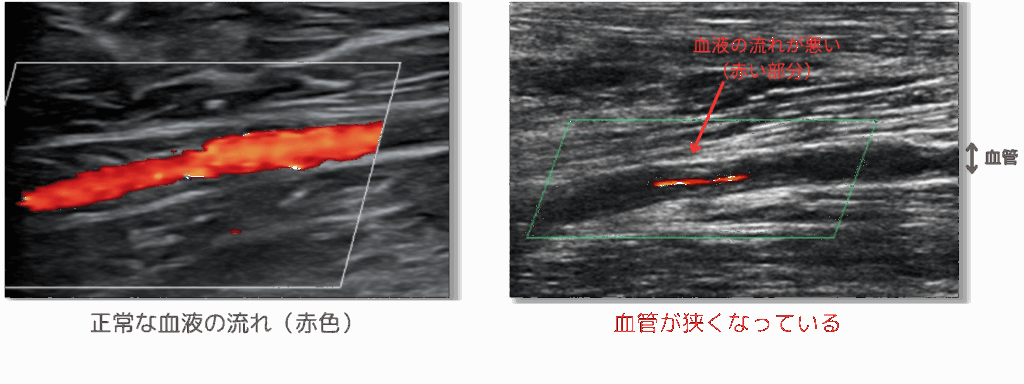

下肢の血管・血流(動脈)ドック

“間歇性破行(かんけつせいはこう)”とは「歩いているとだんだん足が痛くなり、少し休憩するとまた歩ける」といった症状を起こします。これは血管(動脈)が狭くなることで現れる症状です。また、血管が狭くなるまたは詰まると、脳梗塞、心筋梗塞そして突然死などのリスクが高くなります。下肢動脈をエコーで評価することで、早期発見につなげることが可能です。

| 検査の種類 | 検査内容 | |

| 理学的検査 | 問診(既往歴・業務歴)、医師診察 | |

| 血液検査 | LDLコレステロール、HDLコレステロール、中性脂肪、HbA1c | |

| 循環器検査 | 血圧脈波検査:CAVI、ABI | |

| 画像検査 | 下肢動脈エコー | |